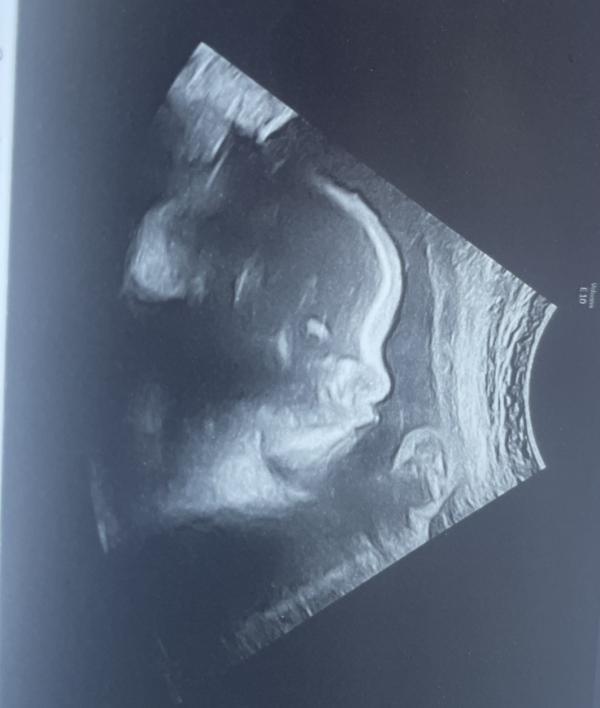

Была сегодня на узи, сынуля маму повеселил от души 😅

Мало того, что сел в тазовое предлежание, так одной рукой с писюном играл, а на другой палец сосал 😂😂😂

Настоящий мужик растёт 😅 потом правда отвлёкся на пузыри и решил их полопать )))